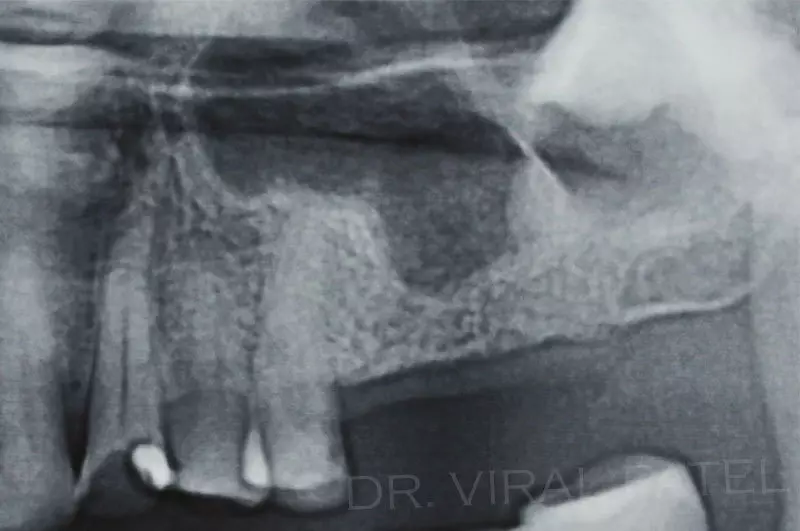

Usually whenever the quantity and quality of bone is compromised, advanced dental implant techniques like bone grafting, sinus graft & sinus bump, ridge augmentation, nerve re-positioning, guided bone regeneration and guided tissue regeneration, platelet rich plasma & platelet rich fibrin and concentrated growth factors are used.

All these recent techniques are also used for bone regeneration & new bone formation.

Furthermore Dr Viral Patel uses digital dentistry techniques for accurate planning of dental implants. Image guided implant place ment has under gone new development in the last few years.

Today, advanced implant systems and the use of Cone Beam CT scans allow experienced dental professionals to insert the implants, and immediately place the new teeth on the implant.